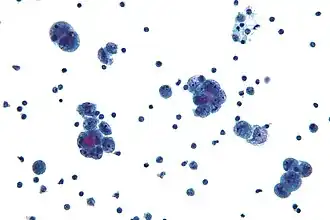

![]() Micrografía de un carcinoma seroso, un tipo de "tumor seroso" | ||

Los tumores serosos forman parte del grupo de tumores epitelial-estromal de cáncer de ovario, derivados del epitelio de Müller. Son neoplasias comunes con una fuerte tendencia a ocurrir bilateralmente, y representan aproximadamente una cuarta parte de todos los tumores de ovario.